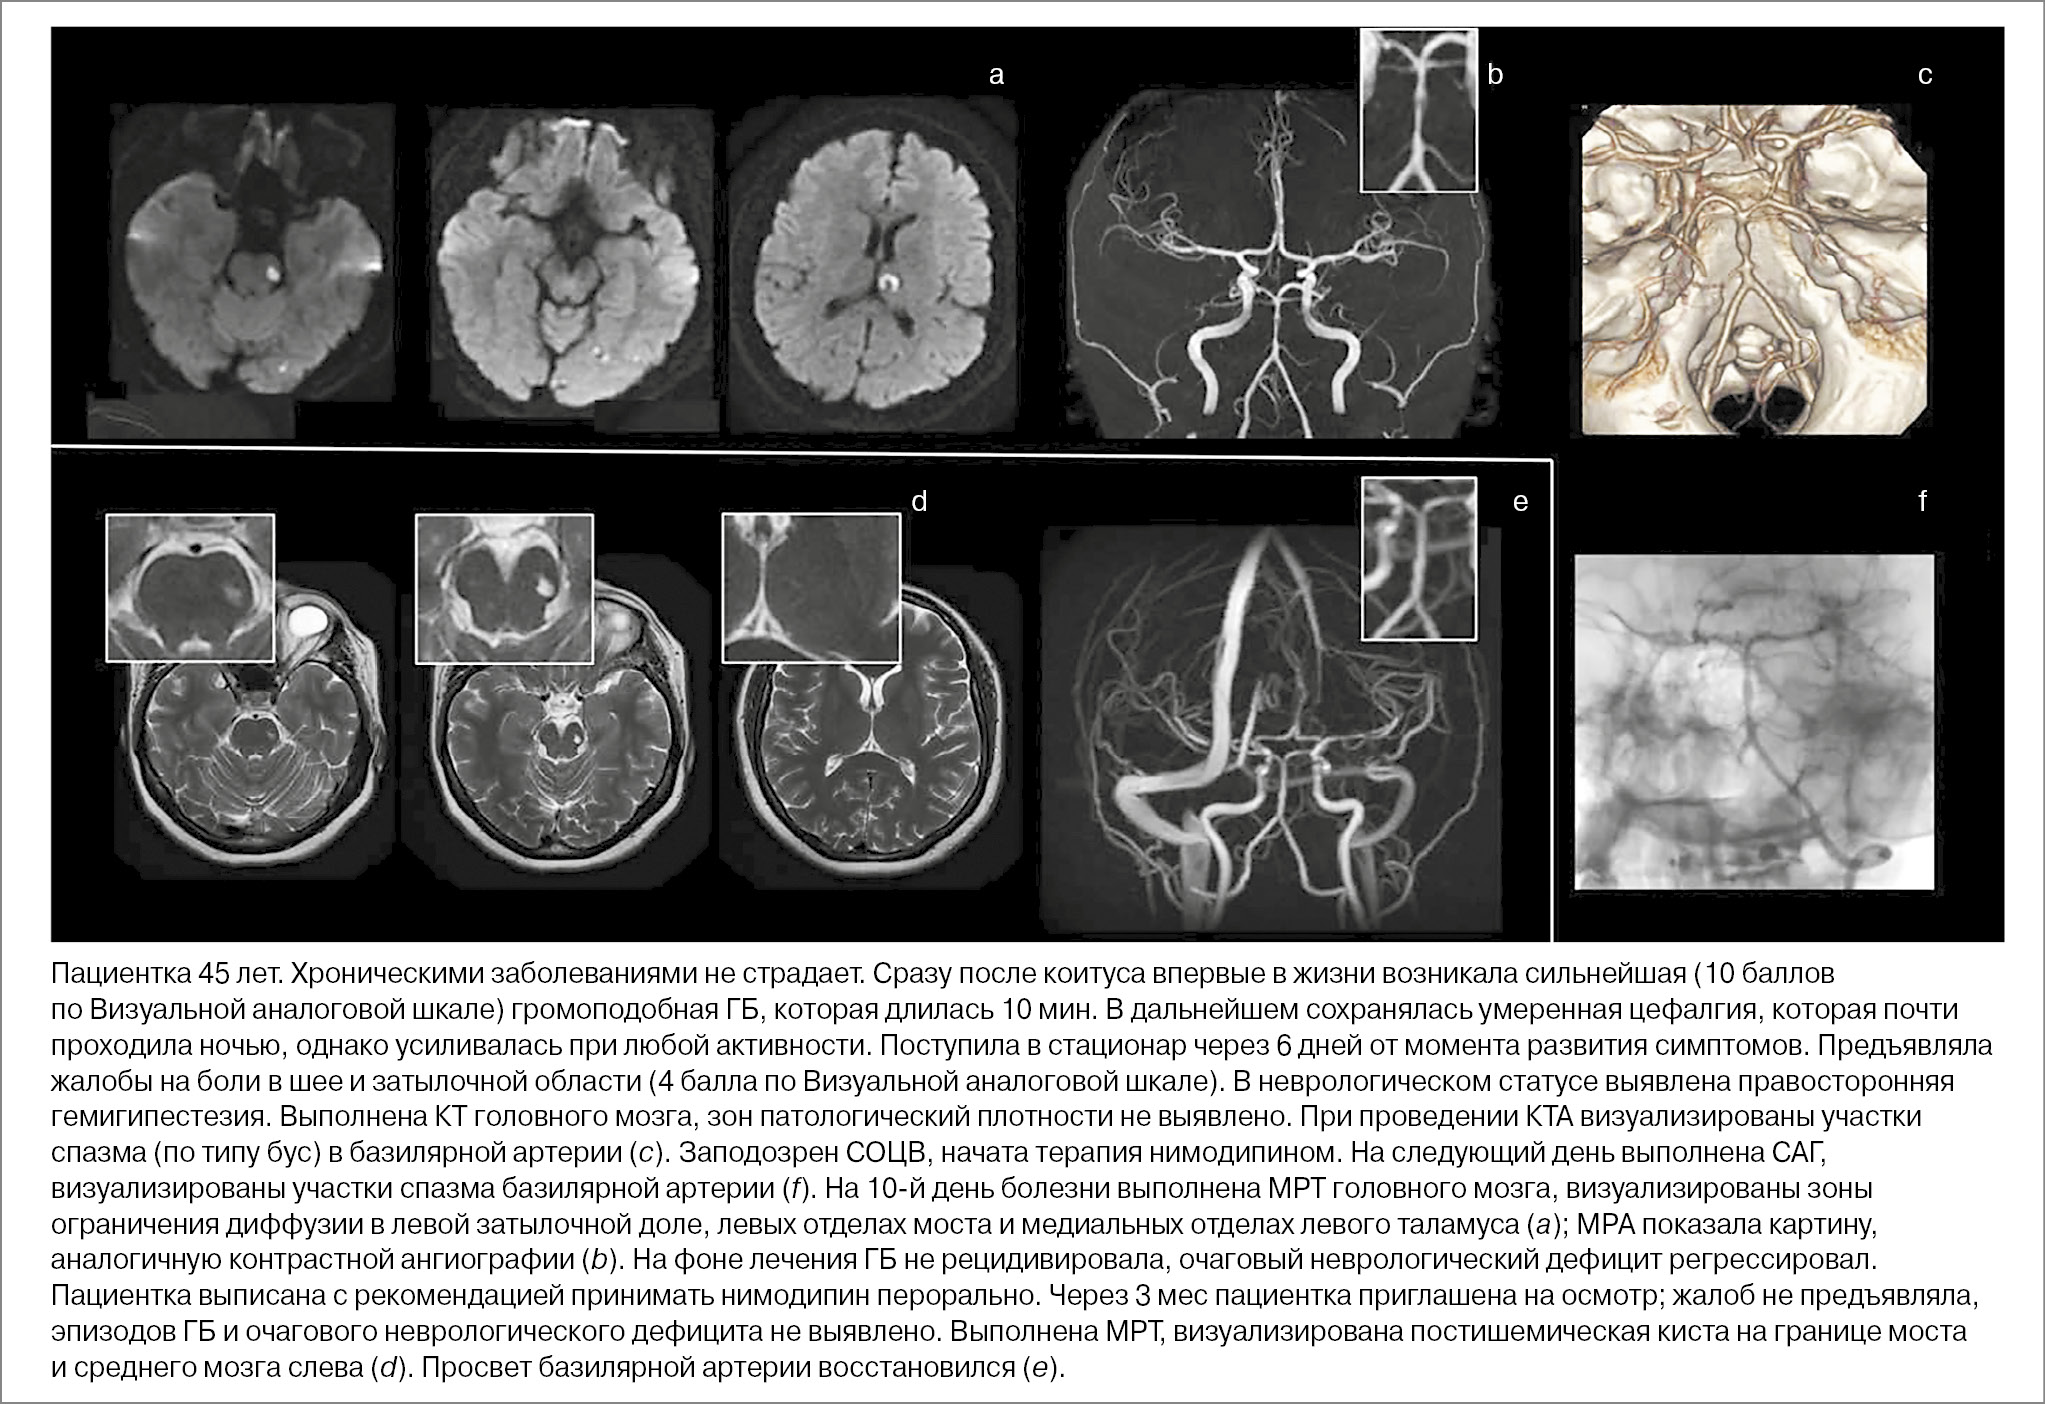

Триггерные факторы СОЦВ. Различные триггеры имеют место у большинства пациентов, к наиболее часто встречающимся относятся прием вазоактивных и наркотических препаратов (41%), беременность и послеродовый период (21%). Основными препаратами (веществами), провоцирующими СОЦВ, являются симпатомиметики (в частности, препараты от насморка), антидепрессанты, наркотики. В каждом 10-м случае СОЦВ провоцируется коитусом (обычно непосредственно перед или во время оргазма) [22]. Приводим клинический пример СОЦВ, спровоцированного коитусом (рис. 2).

Рис. 2. Клинический пример посткоитального СОЦВ.